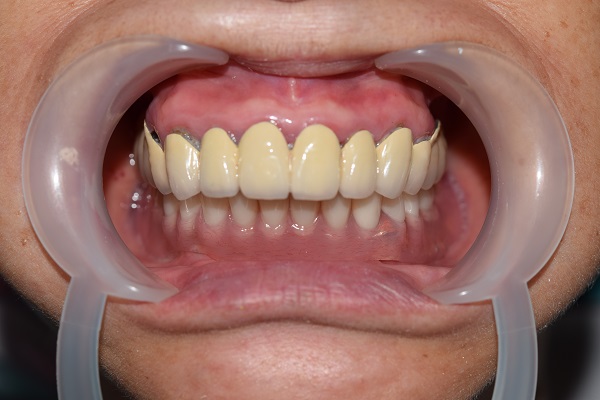

根据术前设计的治疗方案,通过牙槽嵴平整术、植体植入及形成良好的骨结合、二期牙龈手术,袖口形成,模型制取,二次印模,咬合记录,试牙、戴牙等一系列精细的程序,历时大半年多,蔡女士终于戴上了梦寐以求的义齿,无论是咬合、前牙覆盖、笑线及面容外观她都非常满意。她俏皮地说“没想到我还能等到自己有牙的一天,家人为了庆祝我能吃东西,专门请我大聚餐,我终于告别了吃肉糊的日子啦”。